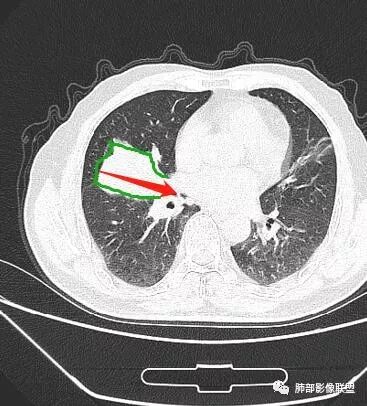

入院CT

老年男性,亚急性病程,咳嗽咳痰。右肺中叶团片影,外朝内分布,大部分边界清楚平直,内侧支气管进入,团片影见低密度坏死区,强化明显,延迟强化,血管破坏不明显,符合爬行征5个特点:

1.肺外周生长。

2.外侧部分体积大于内侧。

3.病变最大径与肺的纵轴及水平面任何一条轴线不平行。

4.病变内侧支气管通畅。

5.病变区域肺容积无缩小。

双侧肺门及纵隔淋巴肿大并可见钙化。考虑结核,但部分边缘膨隆,肿瘤待排。

主病灶在中叶,但是左肺舌段叶有条索影,陈旧病变。蓝色箭头支气管受压,是淋巴结肿大

主病灶在中叶,但是还有结节状病变在下叶

叶间裂推移方向

虽然是一个大的病灶,但是周围是比较散

这个支气管是走形通畅,但是壁增厚的。比较符合炎症改变

下面我们看看支气管都在吗?

内侧段是通畅但是受压的

外侧段一开始狭窄

但是远端通畅,所以我认为支气管都没有堵塞,不太可能是鳞癌

边缘还有多发小灶

淋巴结肿大,钙化。

但是钙化,密度高,没有融合,平扫没有坏死

病灶明显平直,中央是粘液栓,低密度,分界清楚

综上,考虑炎症,结核。